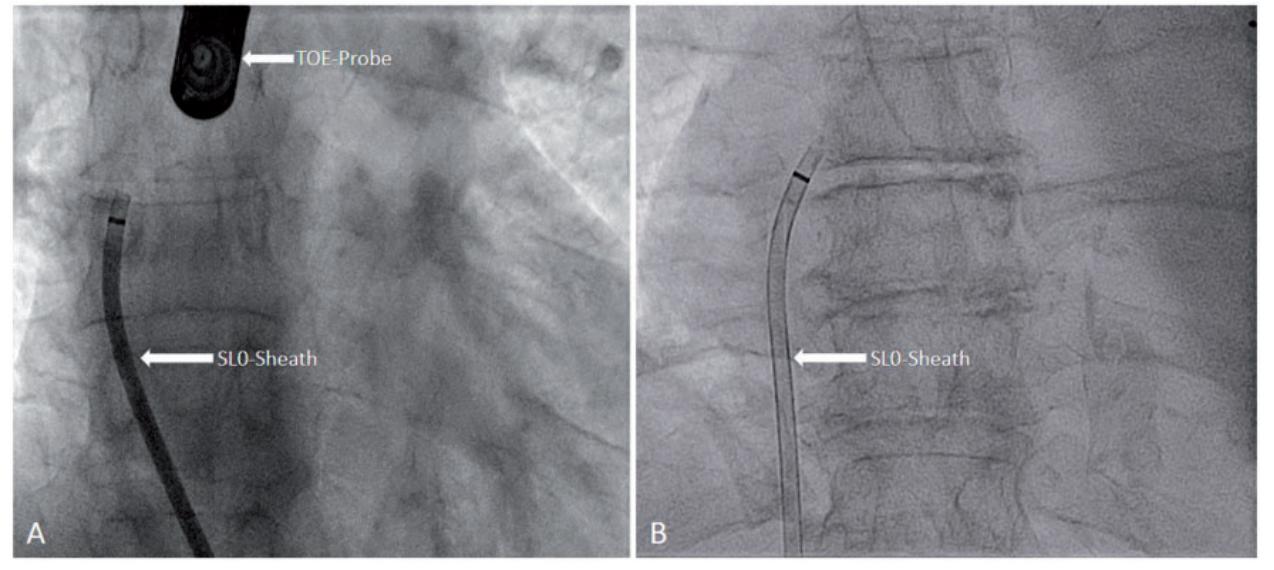

此外,由于不寻常的解剖结构和操作不同鞘管和导管的可能困难,笔者选择cbPVI而不是rfPVI,以便将手术限制为一个可操作鞘管的单次入路。血管通路建立成功。 由于 IVC 的非典型通路和心轴偏离,CSCatheter 的放置再次构成挑战,并被中止以限制机械操作。使用 SL0-Sheath 和标准 BRK-Needle 在 TOE 和透视引导下进行了成功的经中隔穿刺(图 2)。由于间隔壁坚硬,SL0-Sheath 的推进最初失败。

图4: (A) 透视图像(前后投影)显示右心房中的 SL0-鞘,在穿过左侧肝脏后从下腔静脉倾斜上升。 (B) 透视图像(前后投影)显示正常解剖结构患者右心房中的 SL0 鞘处于正常位置。